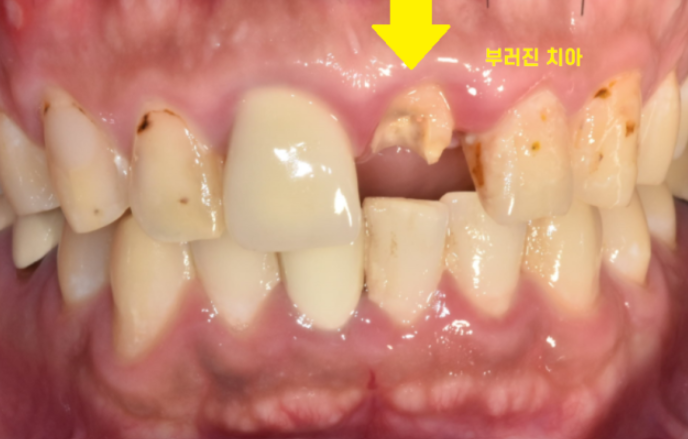

한눈에 봐도 치아가 많이 부러졌습니다.

안쪽에서 들여다보니

신경치료때 사용한 재료가 다 보일 정도로

부러졌습니다.